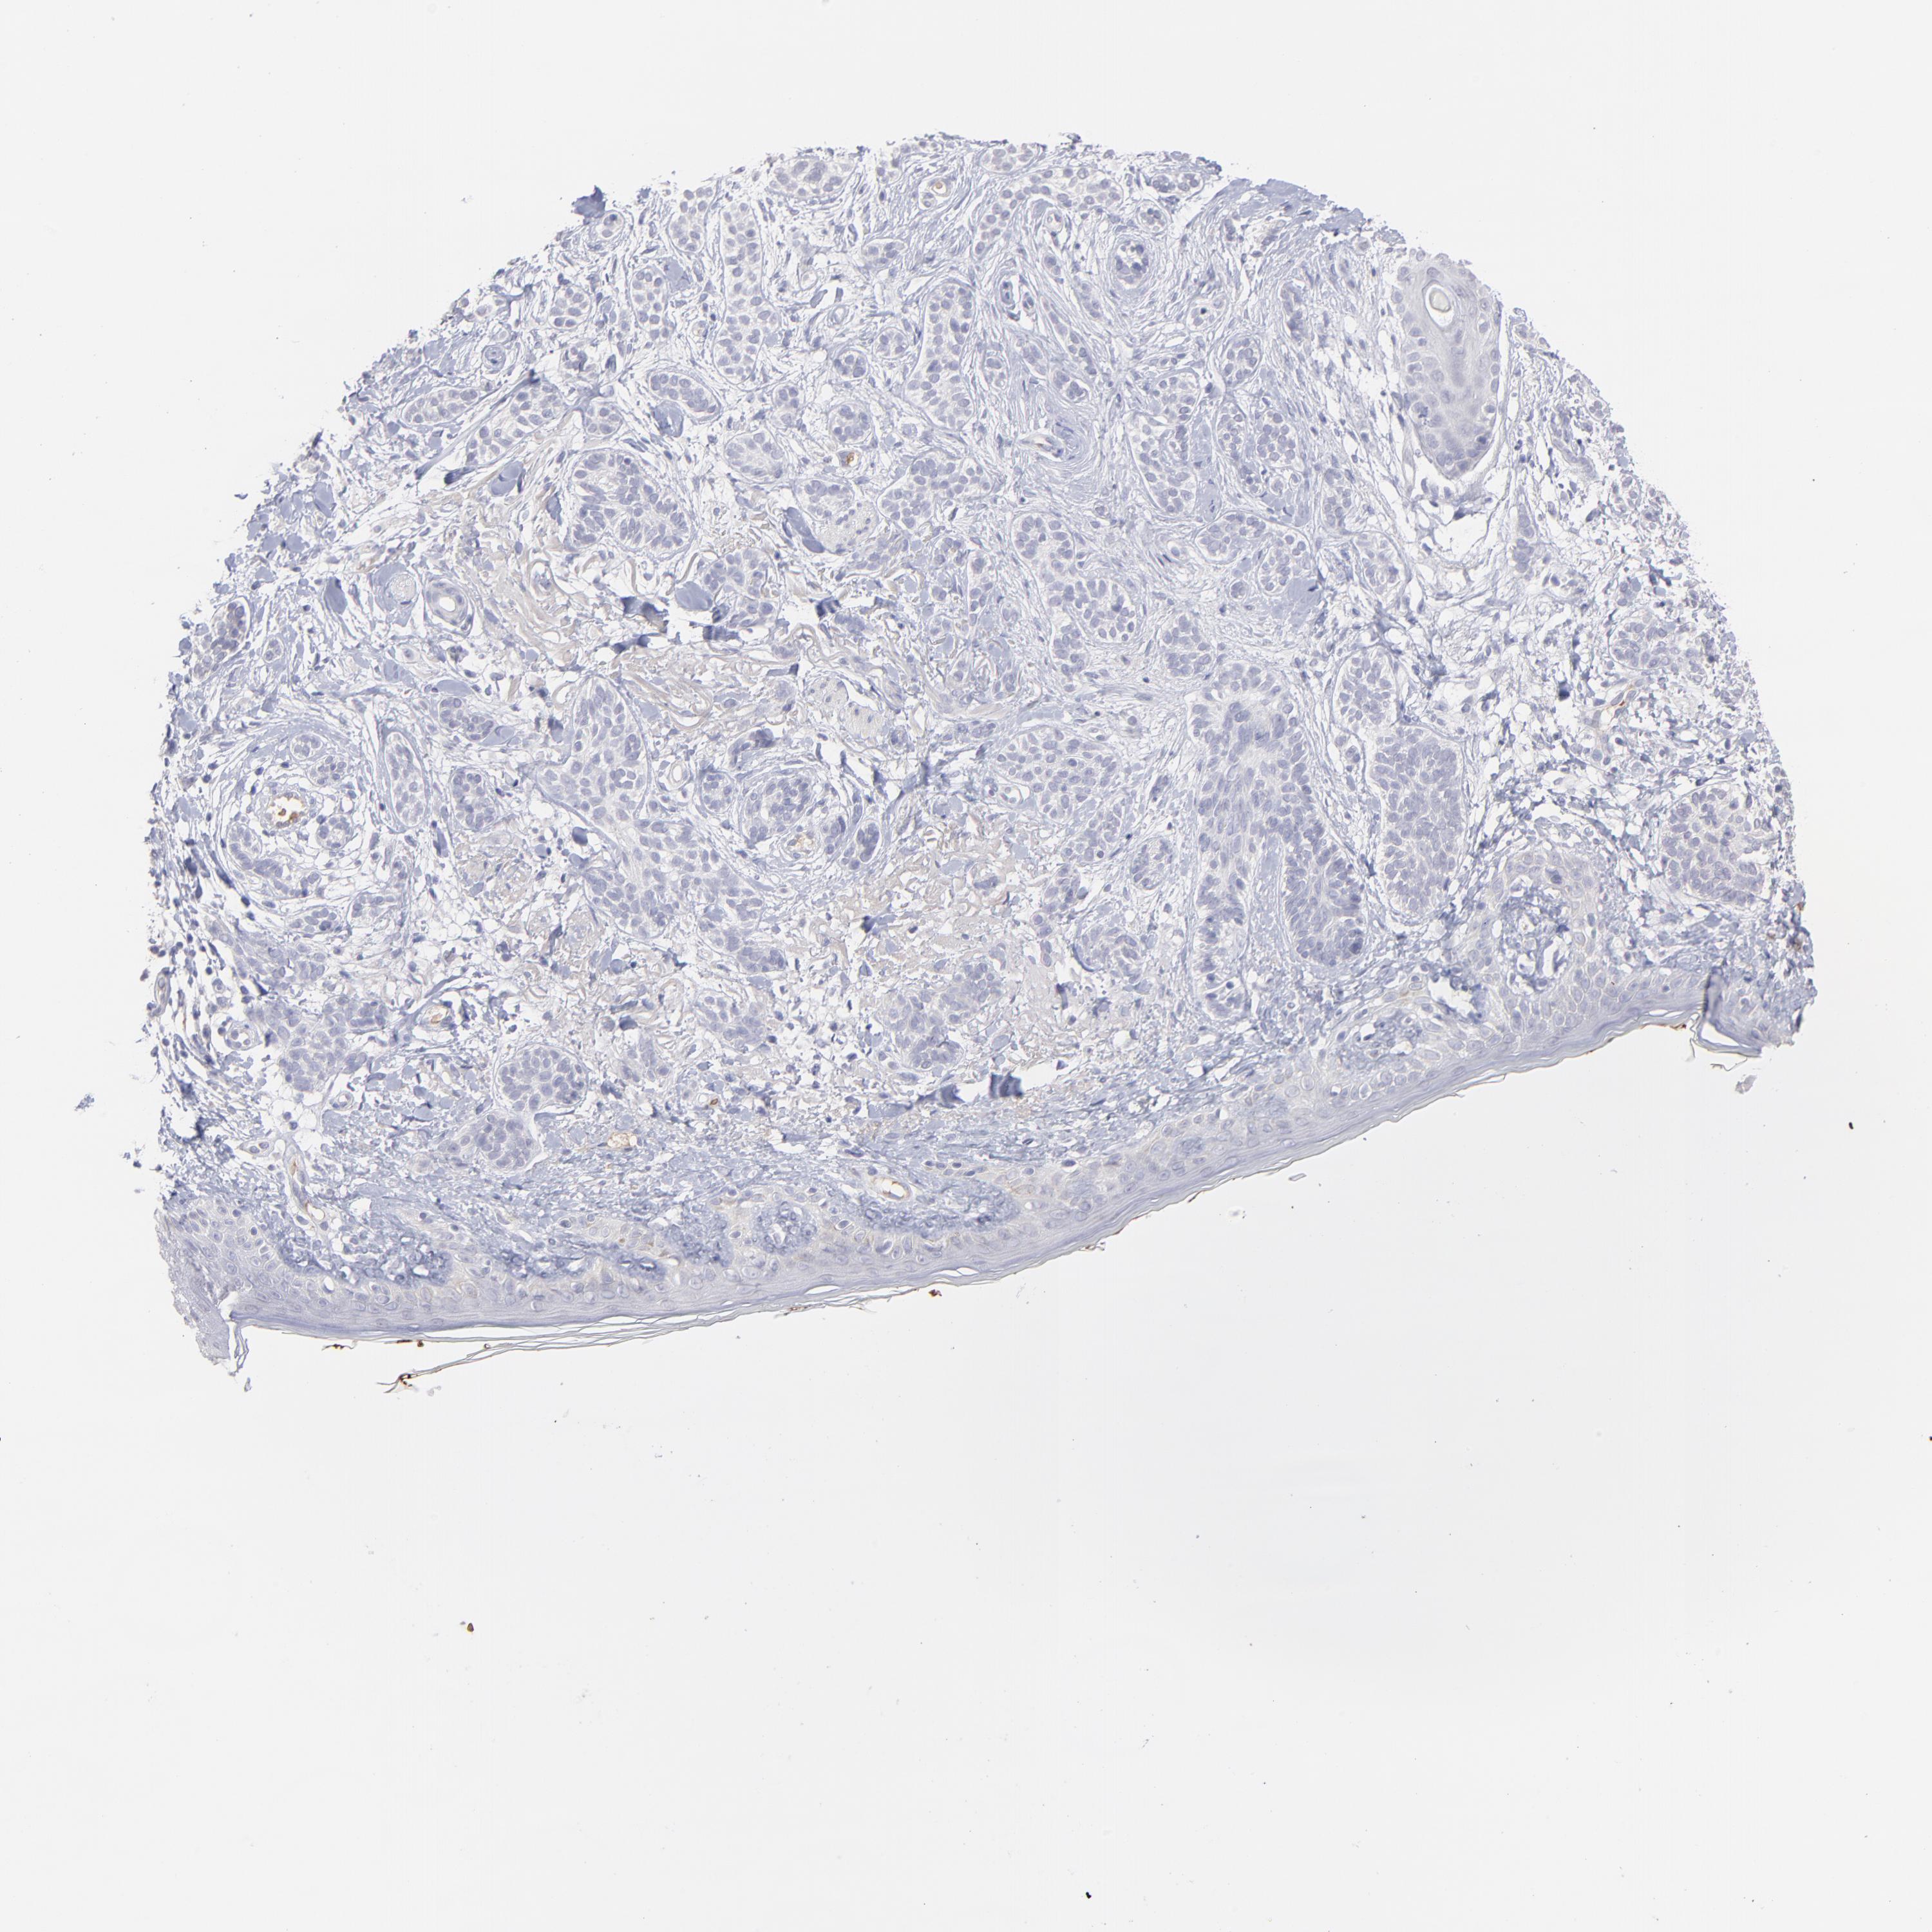

Basal cell and squamous cell cancer

SKIN CANCER - Protein expressioni

A mouse-over function shows sample information and annotation data. Click on an image to view it in a full screen mode. Samples can be filtered based on level of antibody staining by selecting one or several of the following categories: high, medium, low and not detected. The assay and annotation is described here.

Antibody stainingi

Antibody staining in the annotated cell types in the current human tissue is reported as not detected, low, medium, or high, based on conventional immunohistochemistry profiling in selected tissues. This score is based on the combination of the staining intensity and fraction of stained cells.

Each image is clickable and will lead to virtual microscopy that enables deeper exploration of all samples and also displays staining intensity scores, fraction scores and subcellular localization as well as patient and tissue information for each sample.

Antibody HPA003827

Antibody HPA052139

Squamous cell carcinoma, NOS

Basal cell carcinoma